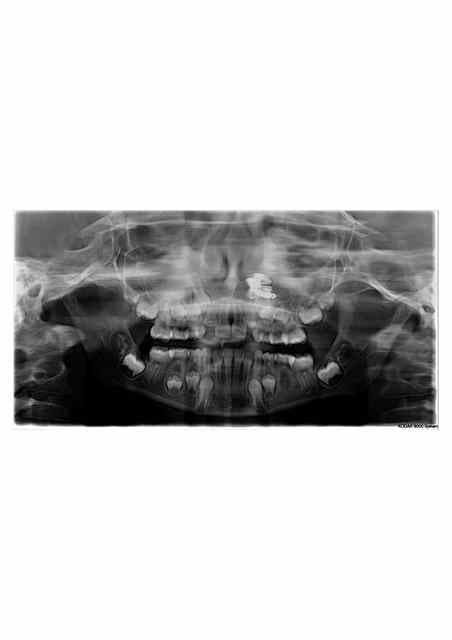

patiente de 9 ans venue pour un trt odf

pano effectuée dans la foulée et là.......surprise.

j'ai demandé un scanner pour mieux visualiser en 3D.

ce ne serait pas un petit jouet inséré par une voie externe?

ça peut etre une explication. c'est justement pour cela que je demande un scan.

le scan me permetra de savoir ou se trouve exactement le corps étranger, et meme de savoir à peu près de quoi il s'agit, ainsi que sa proximité par rapport aux éléments anatomiques voisins.

peut-etre sais tu où se trouve le corps etranger? moi non. je ne pense pas non plus qu'une simple radio pourra te renseigner exactement sur la situation 3D de golgote ou autre morceau de rugine; d'où la pertinence du scan. après si il bouge, ça ne change rien au schmilblick pour l'instant, du moins jusqu'au jour où l'orl devra le retirer

et pourquoi ce ne serait pas tout simplement un corps étranger dans la fosse nasale gauche ?

un petit jouet ?

Elle a peut -être tout simplement mis son doigt dans le nez pendant la pano!) on dirait une main!